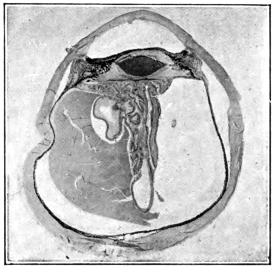

PLATE V.

28.

INJURIES TO UVEAL TRACT

curly bracket span

54

29.

FOREIGN BODY (TIP OF COPPER PROBE) IMBEDDED IN THE EYE

30.

TRAUMATIC DETACHMENT OF RETINA AND CHOROID

31.

WHOLE-SECTION OF FIG. 19

32.

PART OF THE ABOVE MAGNIFIED TO SHOW LENS IMBEDDED IN INFLAMMATORY EXUDATE

33.

PHAGOCYTOSIS